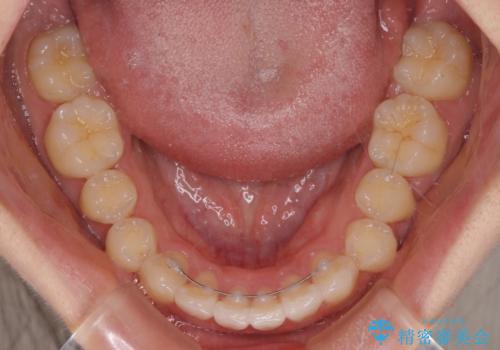

- 前歯のデコボコを気にして来院された患者様です。

前歯が重なっていることで口元が閉じにくくなっていたため、歯列全体の側方への拡大と、歯と歯の間を少し削ってスペースを獲得することとしました。

下顎前歯は後戻りを起こしやすいため、舌側を細いワイヤーで固定し、マウスピース型リテーナーで保定を行うこととしました。